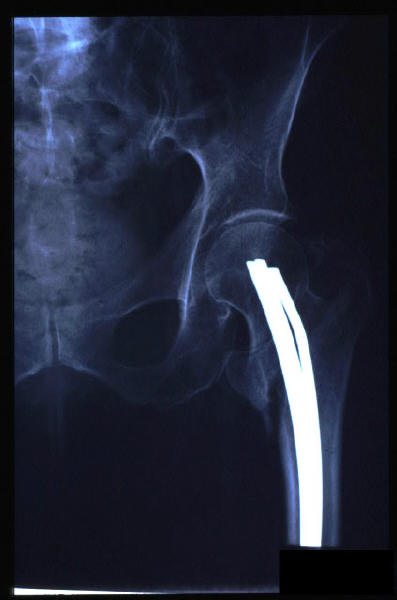

Fractura intertrocantérea de fémur, osteosíntesis